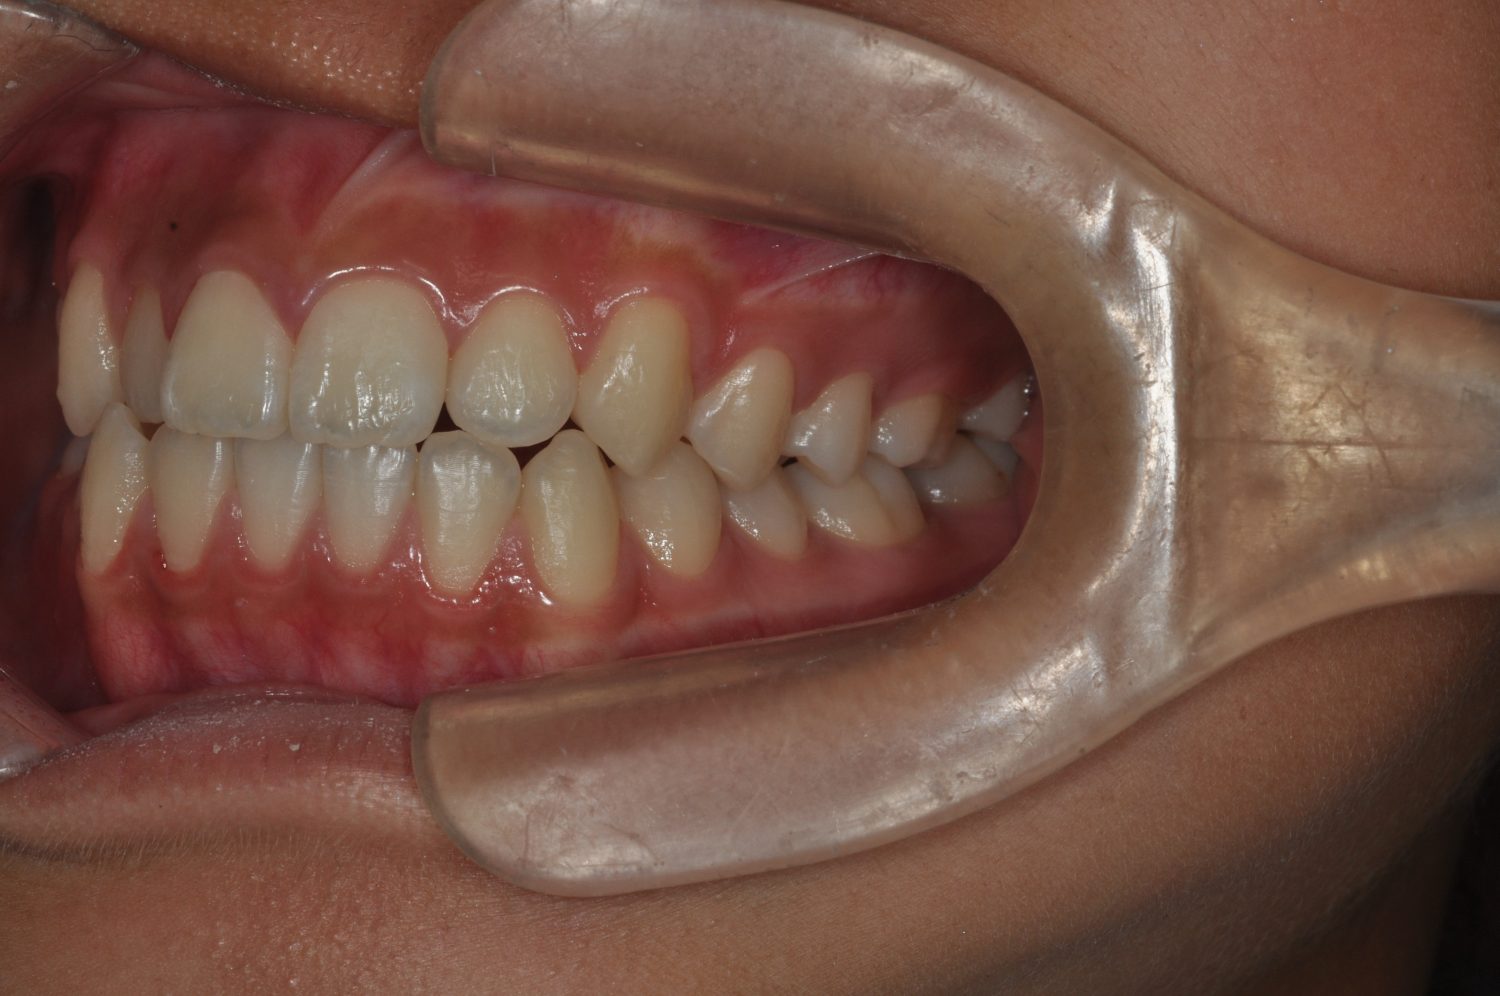

| 主訴 | 前歯の出っ歯を直したい |

| 治療内容 | 上下顎とも標準範囲であるが、上下顎前歯ともに唇側傾斜による、上下顎前突。上顎小臼歯を抜去し配列を行うこととした。 |

| 治療費 | Ⅱ期治療費:770,000円 (税込) 調整料 5,500円 (税込)×23回 保定時:22,000円 (税込) 計 918,500円 (税込) |

| 治療期間 | 2年1ヶ月 |

| 治療回数 | 25回 |

| 想定されたリスク | 矯正器具の装着に伴い、むし歯や歯周病のリスクがありました。また、歯根吸収や歯肉退縮のリスクもありました。 |

上下顎前歯の唇側傾斜による上下顎前突。オーバージェットが大きいため、上顎のみの抜歯で配列を行った。